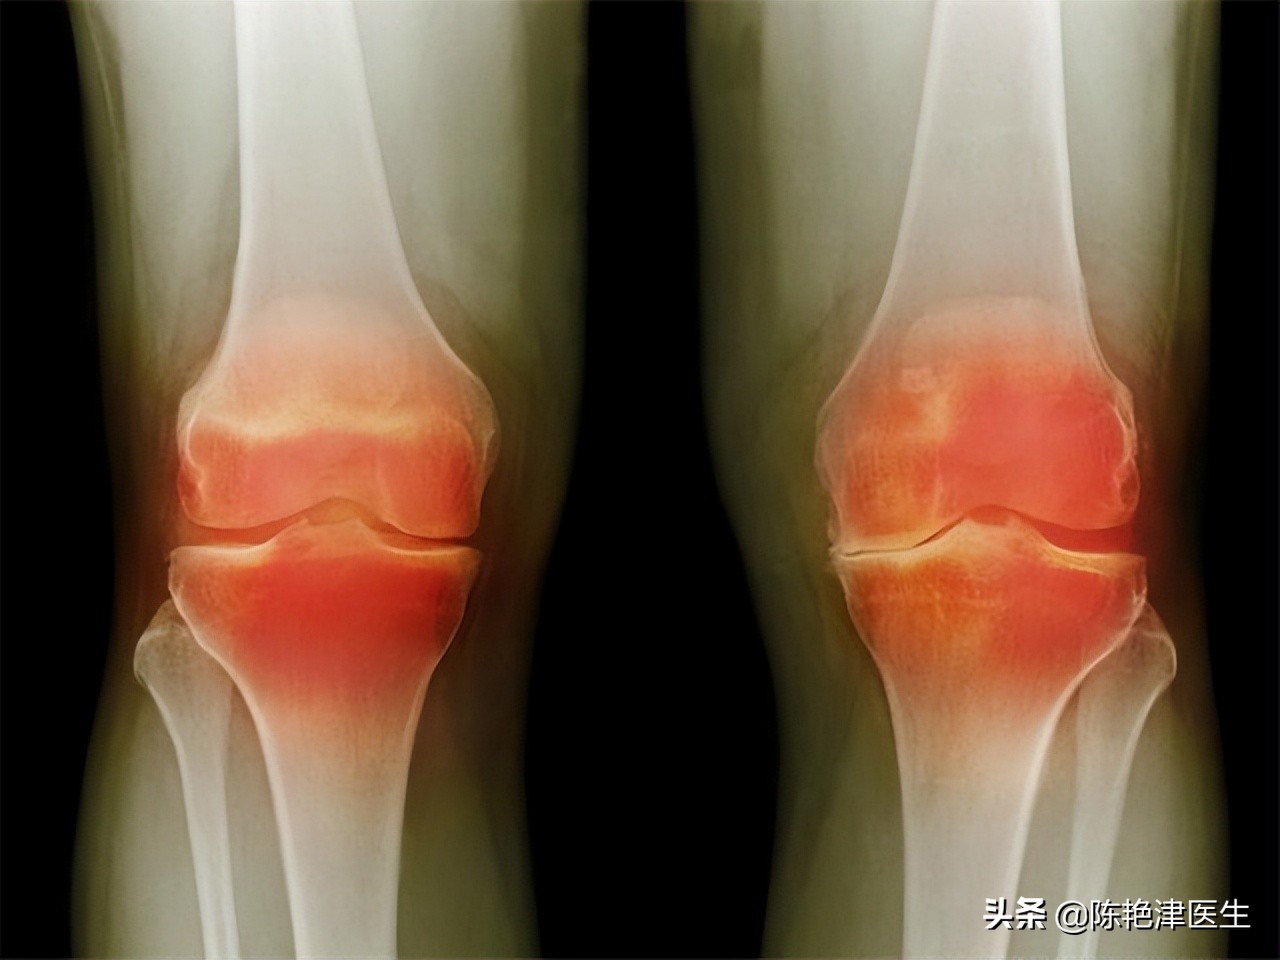

第②种:类风湿性关节炎

类风湿性关节炎是一种病因尚不明确的慢性病,这就导致治愈类风湿性关节炎的难度变得非常大。

类风湿性关节炎主要是以身体骨骼之间的滑膜发炎为主的系统性疾病。 特征是类似手、腿、脚部等小关节、多关节具有对称性、侵蚀性的关节炎症,严重的会导致关节功能丧失。 类风湿性关节炎主要症状是,晨僵,即早晨起床肢体关节活动不灵活。

关节不能受累或受累之后出现疼痛、红肿、发热、发冷等;在发炎部位产生囊肿等。其他并发症有心脏受累后产生心脏相关疾病,比如心包炎等;呼吸系统受累之后产生胸腔积液、肺炎等呼吸系统疾病;肾脏也可能会受拖累患原发性肾小球及肾小管间质性肾炎等疾病,严重的会影响肾功能。同时还会引发贫血、行动不便、神经系统受损等疾病。

该病难以治疗的原因是本病的病情本身, 本病是一种自身免疫性疾病,多数患者血清当中存在自身抗体。 目前治疗该病所选用的治疗方式大多数都是使用对人体免疫系统有危害的激素类药物,暂时缓解症状,并不能从根本上解决疾病问题,而且长时间服用激素类药物还有可能导致药物依赖,随着运动量的增加,日后必须服用更大剂量的药物才能控制住症状。

迄今为止,还没有治愈这种疾病的方法,而 治疗的主要目标是缓解疼痛、控制症状、提高生活质量和预防危险的并发症 ,类风湿性关节炎病人应积极配合医生选择自己最适宜的治疗方案。只有经过病人和医生积极配合,医生在临床中反复思考研究,才能摸索到最合理的治疗方法使病人尽快康复。